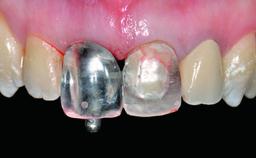

Replacement of an Ankylosed Upper Left Central Incisor: Bone Augmentation and Socket Grafting, Late Placement of an RC Bone Level Implant

Prosthesis Type FDP

Defining Characteristics One missing tooth to be replaced by an implant-borne crown

Provisional Implant-Supported Prosthesis Prosthodontic margin > 3 mm apical to mucosal margin Prosthodontic margin > 3 mm apical to mucosal margin